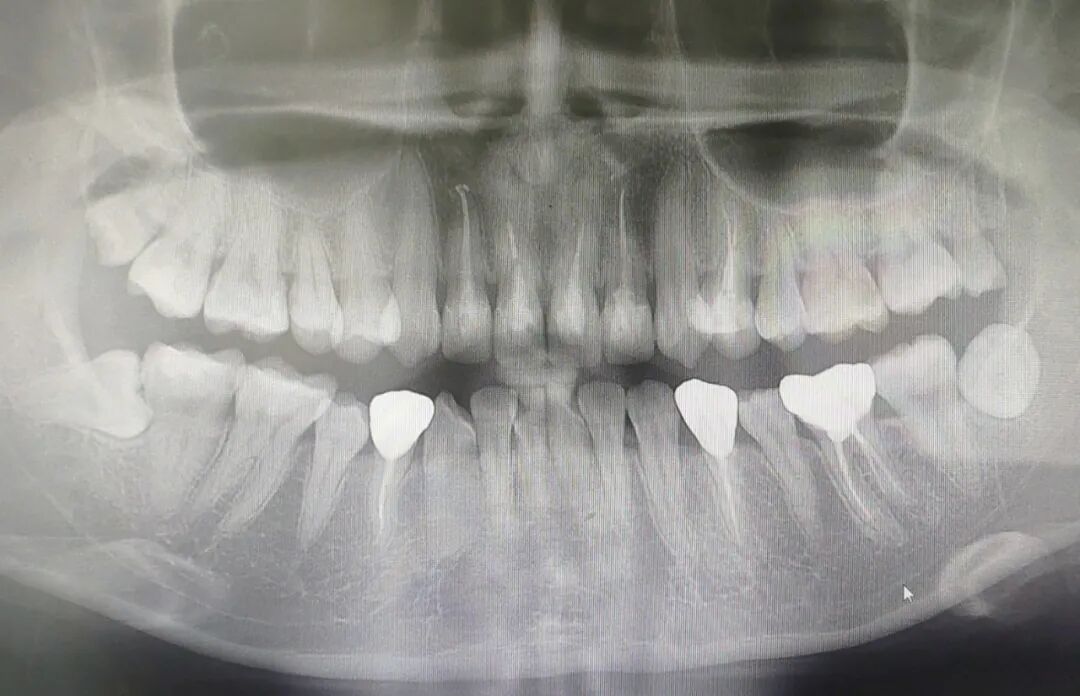

由于周女士之前日常没有做好清洁牙齿的工作,再加上本身就较容易蛀牙,第一次找到林医生的时候,已经有了不少龋齿,其中四颗已经转为慢性牙根尖周炎,需要做根管治疗。

针对李女士前牙修补材料易脱落和其中一个门牙扭转,林医生选择通过做牙冠的方式一次性解决,同时还补好了她其余牙齿的龋坏部分。